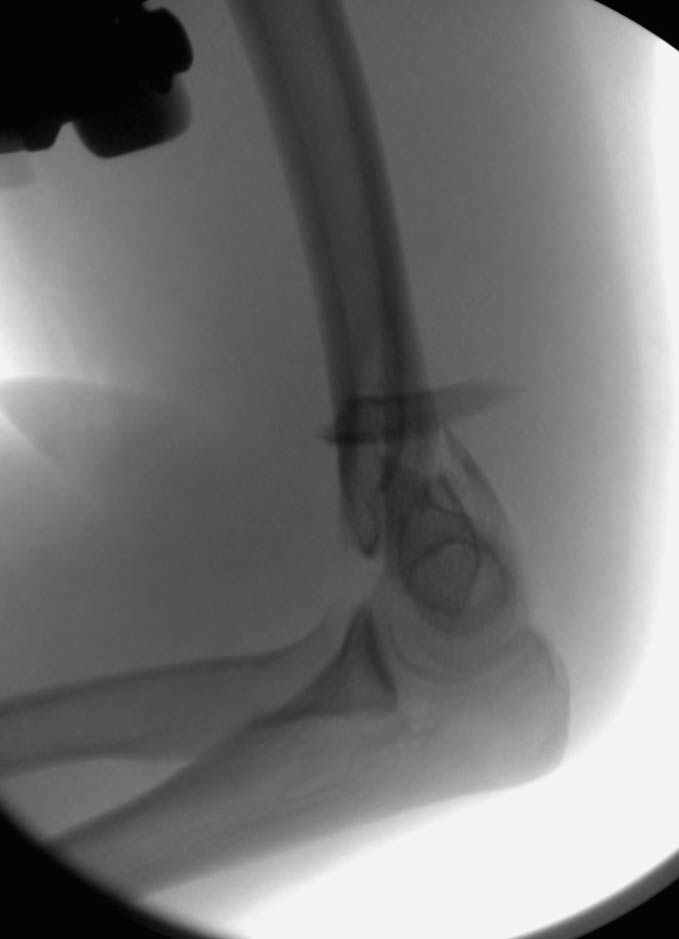

Примерный случай, только перелом был открытый, в задне-медиальной стороне рана около 2 см по характеру "изнутри кнаружи", неврологический статус со слабостью сгибания мизинца, также слабая абдукция и аддукция указательного пальца и сгибания в кисти.

Больному сделали обработку и наложили временный аппарат внешной фиксации плечо-предплечье.

Этапы операции на снимках....